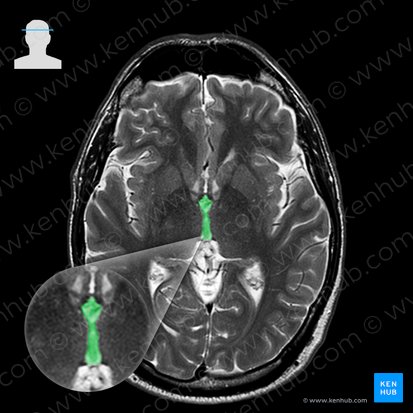

The brainstem is the distal part of the brain that extends from the base of the brain to the spinal cord. From superior to inferior, the brainstem consists of the midbrain, pons and medulla oblongata. Each of them features many important structures such as the cranial nerve nuclei. The axial section of the midbrain is often said to resemble Disney's character Mickey Mouse. On many normal scans, nothing more than the shape of the brainstem is clearly distinguishable. However, you can map the brainstem by using the Mickey Mouse map:

• The cerebral peduncles are presented as the ears of the mouse. Just medial to each peduncle is the substantia nigra.

• The two red nuclei (not easily seen in MRI images) are presented as Mickey’s eyes, while the nucleus of the oculomotor nerve (III) and the medial longitudinal fascicle comprise the nostrils.

• Lastly, the cerebral aqueduct and the periaqueductal grey matter, which are found in the central part of the midbrain, form the mouth of Mickey Mouse.